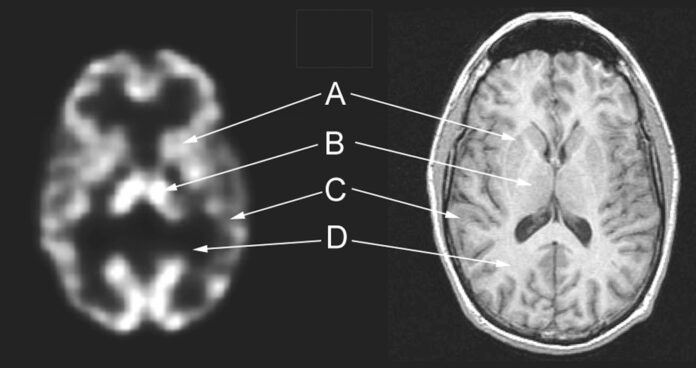

Brain SPECT imaging is a functional imaging technology that helps clinicians see how different regions of the brain are working in real time. Unlike traditional scans such as MRI or CT, which focus on the physical structure of the brain, SPECT visualizes blood flow patterns and metabolic activity. This paints a clearer picture of how the brain functions beneath the surface. It is especially valuable for diagnosing conditions that may not show up on structural scans, such as depression, ADHD, traumatic brain injury, dementia, and various neurological disorders.

At its core, brain SPECT imaging uses small amounts of radiotracers, which are safe pharmaceutical compounds that emit gamma rays, to highlight how well blood flows to different brain regions. Areas with healthy function show normal blood flow, while dysfunctional areas may appear cold (low activity) or hot (overactivity). These visual patterns give clinicians insight into how the brain is performing and help guide personalized treatment plans.

Brain SPECT imaging, short for Single Photon Emission Computed Tomography, sits at the intersection of nuclear medicine and advanced diagnostic imaging. What makes SPECT unique is its ability to capture how the brain behaves rather than simply what it looks like.

The science behind SPECT centers on the concept of cerebral perfusion, or the movement of blood through the brain. Because blood flow is directly linked to function by providing oxygen, glucose, and essential nutrients, measuring perfusion allows clinicians to assess brain activity. Regions with healthy blood flow are typically functioning normally, while areas with reduced perfusion may indicate injury, inflammation, or degeneration.

This method allows clinicians to see not only which regions are active but also how different areas communicate and coordinate. Functional abnormalities such as underactive frontal lobes, overactive limbic regions, or uneven perfusion patterns become visible in ways that structural scans cannot reveal.